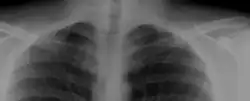

A cervical rib in humans is an extra rib which arises from the seventh cervical vertebra. Their presence is a congenital abnormality located above the normal first rib. A cervical rib is estimated to occur in 0.2%[7] to 0.5%[8] (1 in 200 to 500) of the population.[9] People may have a cervical rib on the right, left or both sides.[10][11]

Most cases of cervical ribs are not clinically relevant and do not have symptoms;[12][13] cervical ribs are generally discovered incidentally, most often during x-rays and CT scans.[8][9][11] However, they vary widely in size and shape,[8] and in rare cases, they may cause problems such as contributing to thoracic outlet syndrome,[12] because they press on the nerves.[12][14]

On imaging, cervical ribs can be distinguished because their transverse processes are directed inferolaterally, whereas those of the adjacent thoracic spine are directed anterolaterally.[16]